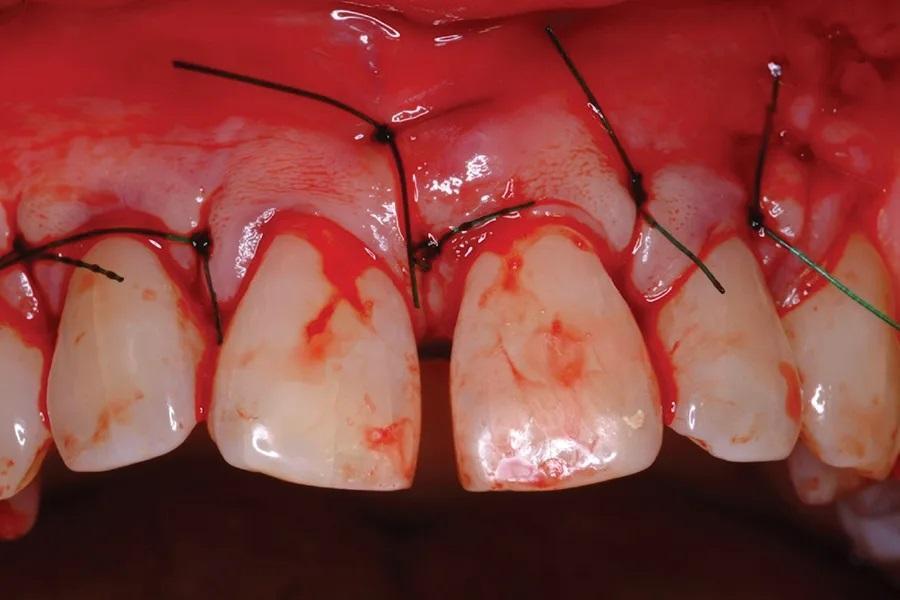

Фото 8. Слизисто-надкостничный лоскут был ушит.

Затем участок был покрыт БоТФ (Фото 7), чья консистенция, подобная десне, предотвращала рассеивание костного трансплантата по линии разреза лоскута. Это было особенно важно, поскольку защитная (коллагеновая) мембрана не применялась. Впоследствии мягкие ткани были ушиты (Фото 8).